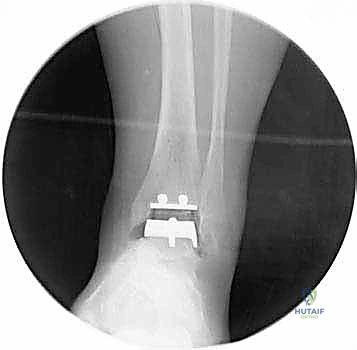

4. وضع أدلة القطع (Jig Placement and Alignment)

تعتمد دقة الجراحة على المحاذاة الصحيحة. يتم استخدام أجهزة توجيه متطورة (Jigs) تثبت على عظمة الساق باستخدام دبابيس معدنية. يتم التحقق من صحة الزوايا والمحاور باستخدام جهاز الأشعة السينية المباشر داخل غرفة العمليات (C-arm Fluoroscopy). يضمن الدكتور هطيف أن يكون القطع موازياً للأرض تماماً عند وقوف المريض.